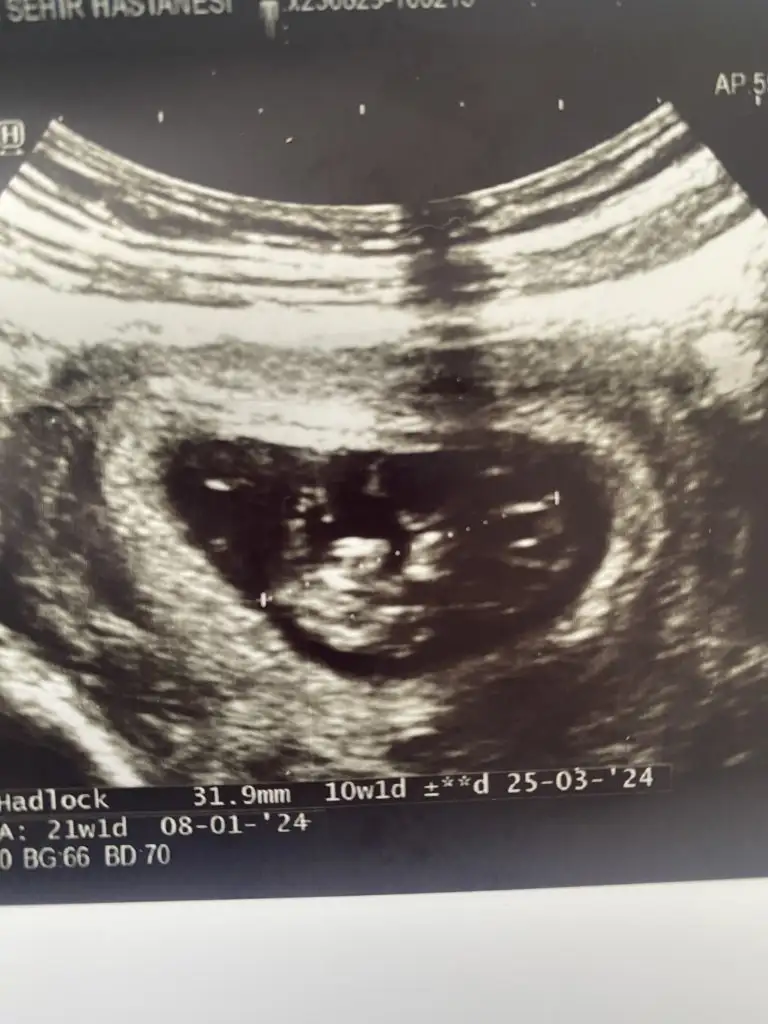

Kiza benziyor saglikla gelsinEki Görüntüle 3293892 Bizede tahmin yapabilir misiniz 10 haftalığız merak ediyorum çok sevinirim :)

Birazcık küçüğüz sanırım hafta olarak. Kız gibi ama ilerleyen haftalarda tekrar baksak iyi olur.Bize de tahminde bulunur musunuz